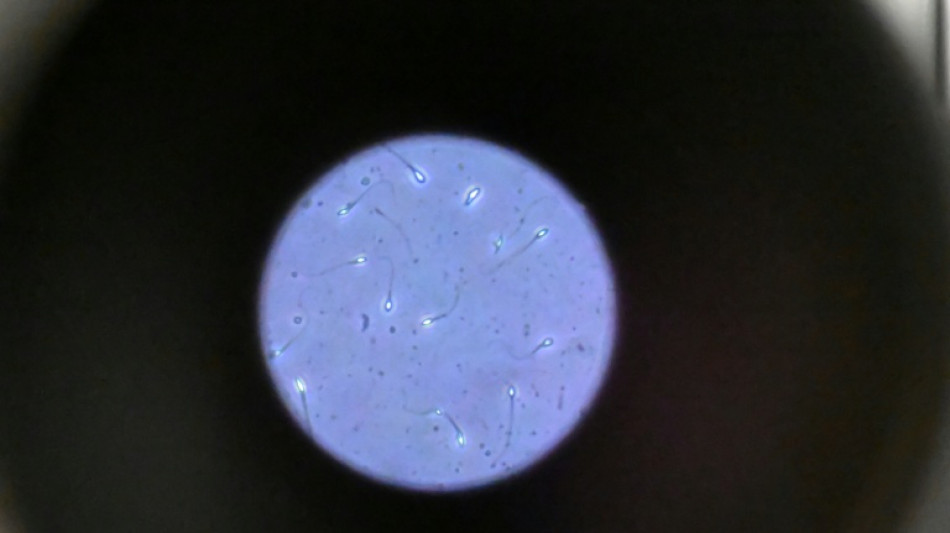

Dans l'espace, les spermatozoïdes ont du mal à trouver leur chemin

Dans l'espace, les spermatozoïdes ont du mal à trouver leur chemin vers l'ovule en raison de la microgravité, qui perturbe aussi le développement des embryons, selon une étude publiée jeudi dans Communications Biology.

Une des difficultés réside dans le fait que le sperme n'est plus attiré vers le bas par la gravité terrestre.

"Les spermatozoïdes doivent activement trouver leur chemin vers l'ovule et cette étude est la première à tester leur capacité à le faire dans des conditions semblables à ce qui se passe dans l'espace", explique à l'AFP Nicole McPherson, autrice principale de l'étude et chercheuse à l'Université d'Adelaïde (Australie).

Son équipe a utilisé une chambre en plastique imitant l'appareil génital féminin, qui leur a servi de "parcours d'obstacles miniature". "Voyez ça comme un minuscule circuit de course... Les spermatozoïdes étaient introduits à une extrémité et devaient nager jusqu'à l'autre bout", décrit-elle.

Les chercheurs ont testé successivement du sperme de souris et humain dans ce dispositif placé dans un appareil en constante rotation pour simuler la microgravité.

Les gamètes ont été environ 50 % moins performants pour naviguer à travers ce parcours que sous la gravité terrestre. Cela équivaut à une baisse de 30% du taux de fécondation réussie, selon les résultats de l'étude.

Les spermatozoïdes ayant réussi à franchir le parcours semblaient produire des embryons de meilleure qualité.

Il semble que le stress lié à la microgravité ait agi comme un "filtre" éliminant les plus faibles et "ne laissant en lice que les plus performants", ce qui pourrait s'avérer "bénéfique", selon Mme McPherson.

Cependant, un problème plus important est apparu dans les vingt-quatre heures suivant la fécondation.

"Les résultats se sont brutalement inversés, avec moins d'embryons formés. Et ceux qui restaient étaient de moins bonne qualité", note la chercheuse.

La microgravité "n'est peut-être pas l'obstacle insurmontable que nous craignions, mais protéger les embryons de l'impesanteur au cours de ces premières heures critiques sera vraisemblablement essentiel pour la reproduction dans l'espace", avance Mme McPherson.

De nombreuses autres recherches seront cependant nécessaires pour comprendre comment la reproduction fonctionne dans l'espace, la fécondation n'étant qu'une "petite pièce d'un très grand et complexe puzzle", ajoute-t-elle. "Nous sommes encore très loin de voir un premier bébé de l'espace"!